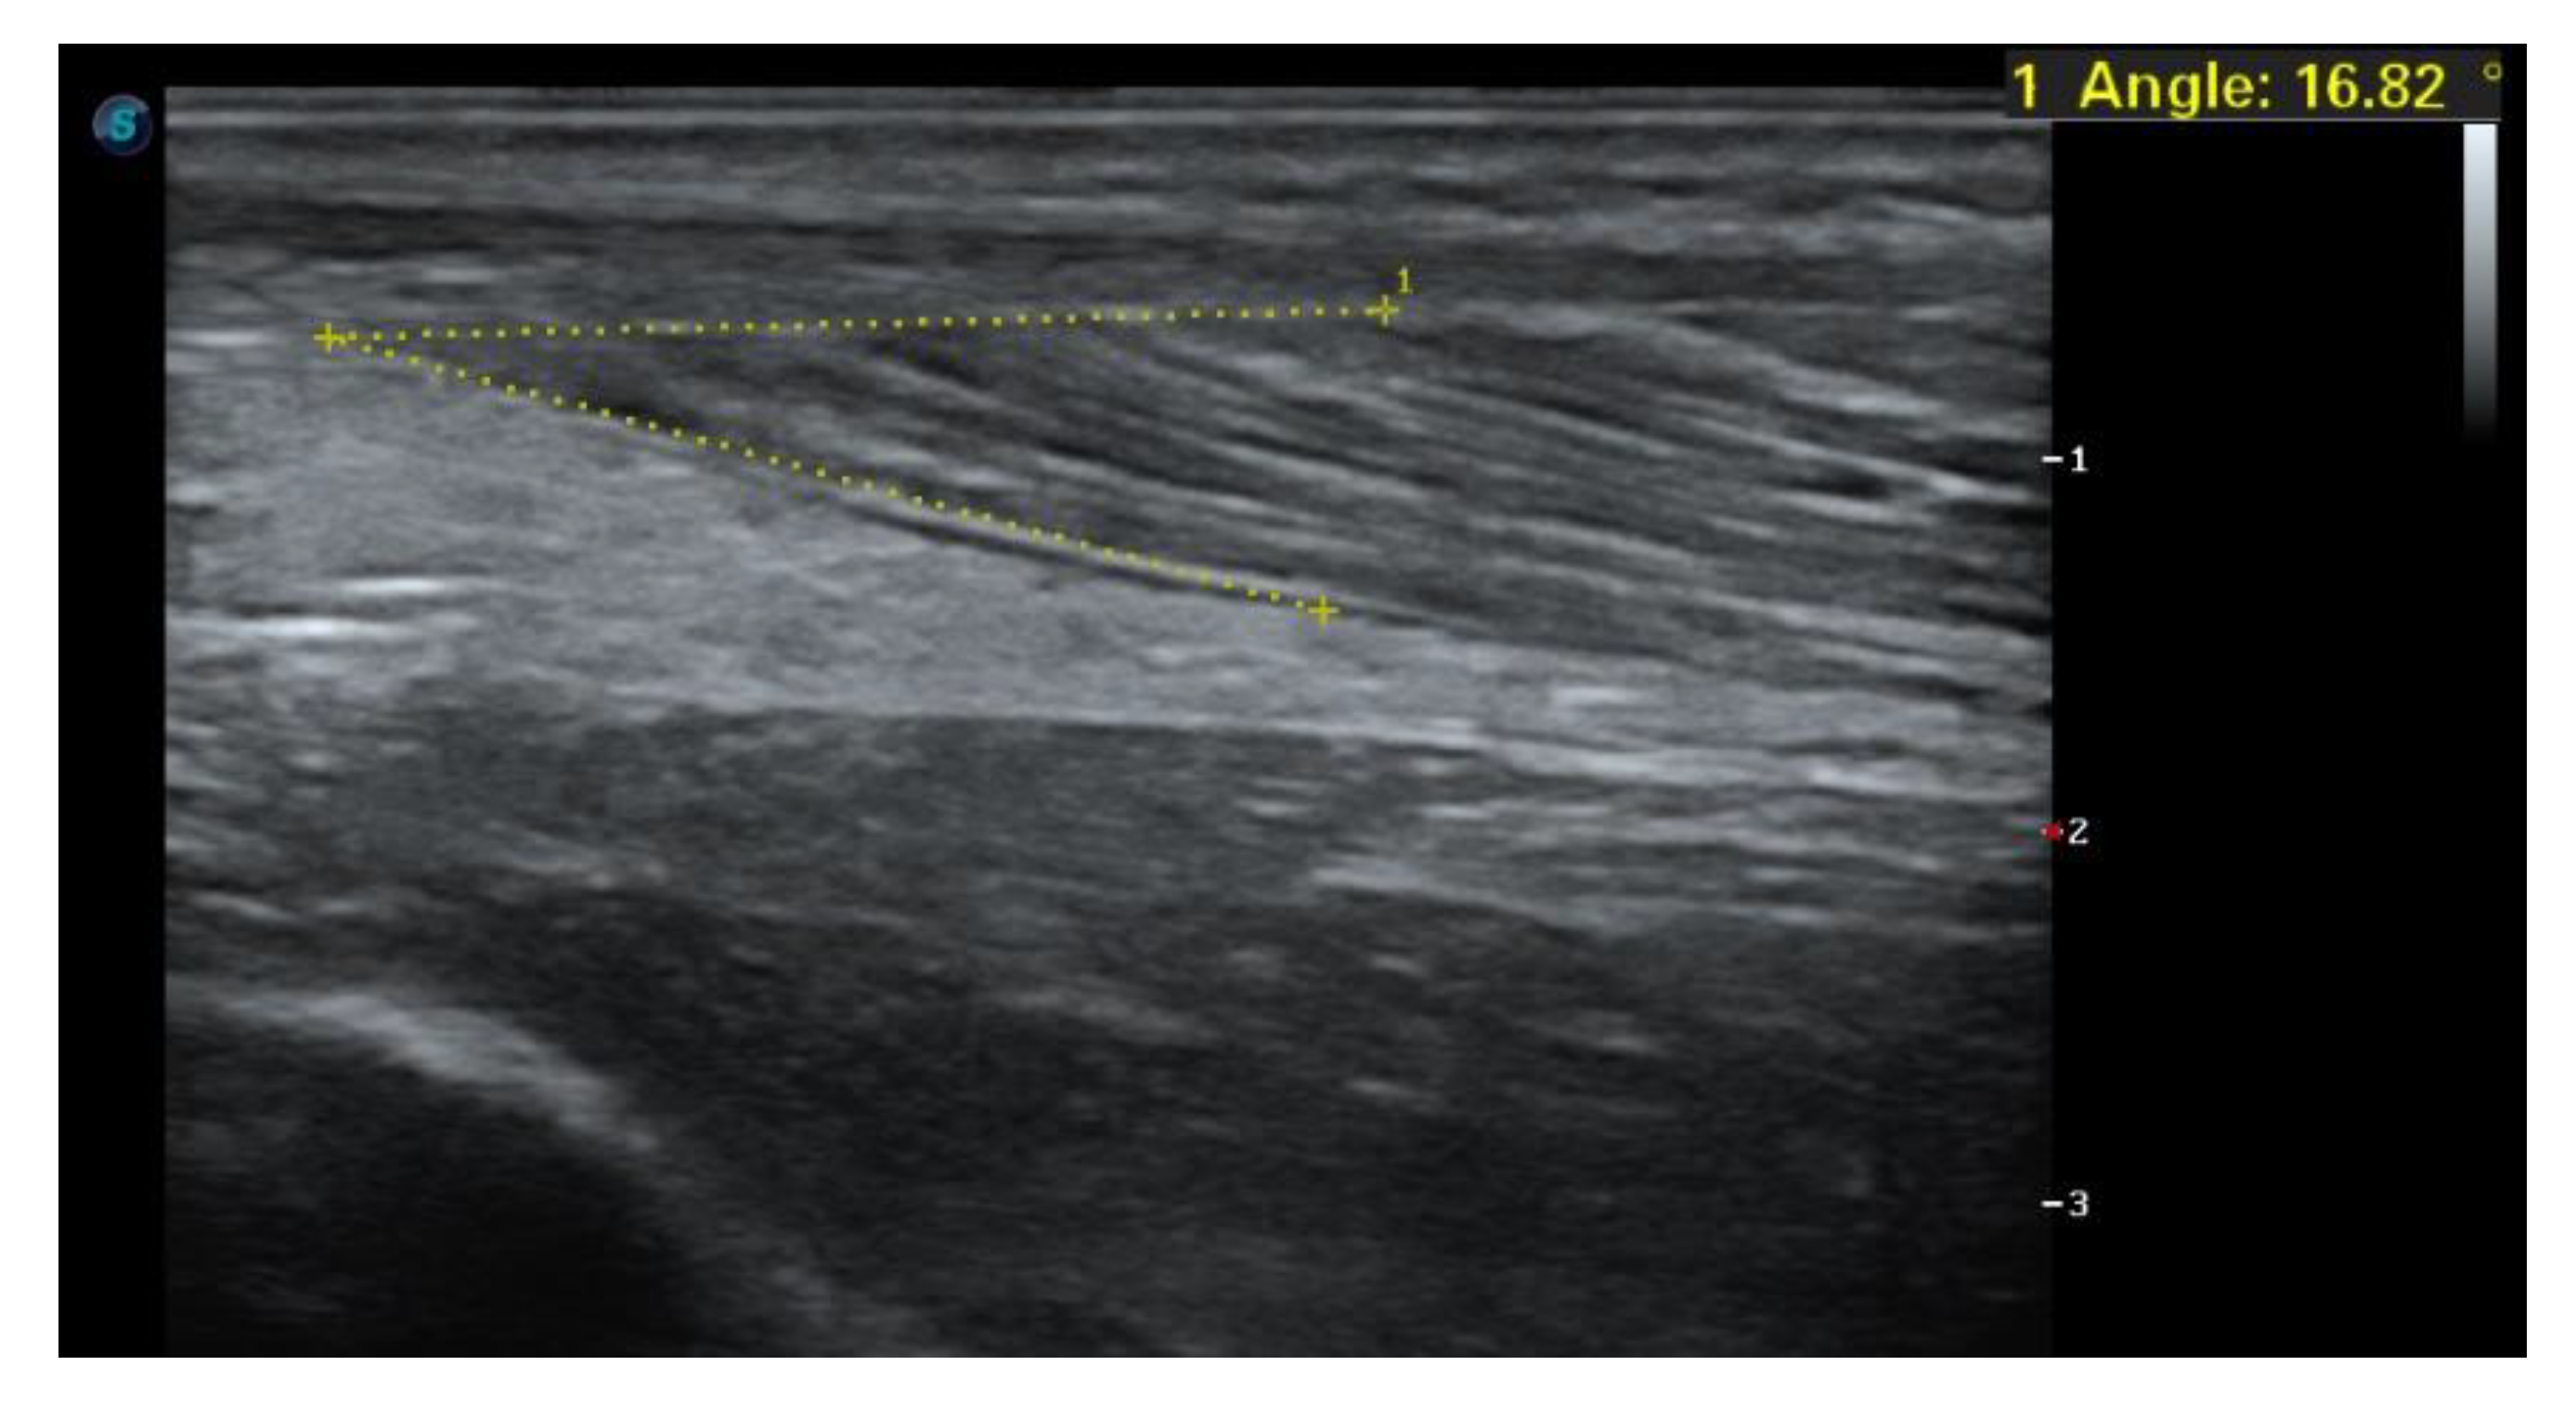

1.4. Case Report

1.5. Imaging Tests